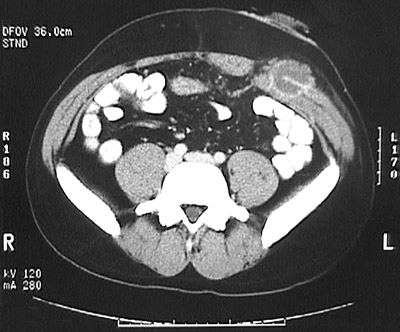

This abdominal CT scan reveals an abscess that resulted from a fistula that formed adjacent to a colostomy that was necessitated by removal of colon with a severe granulomatous colitis.